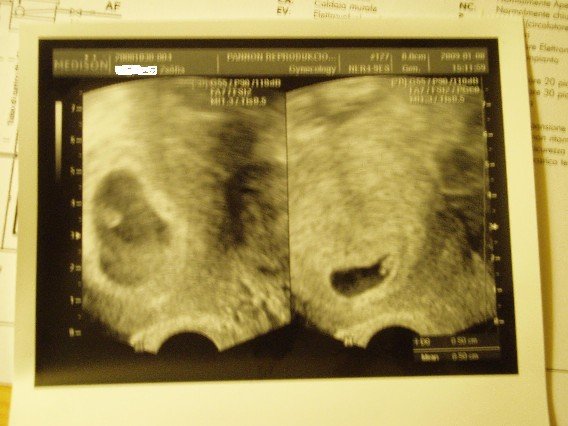

Van róluk képem is, 8-án 5 mm-esek voltak és vert a szívük.

Kép

KépKép

Két petezsákban vannak, külön-külön. A képen is látszik, külön lettek fotózva. Egyikben egyik Baba, másikban a másik. Amúgy elég közel vannak egymás mellett odabent. :wink: